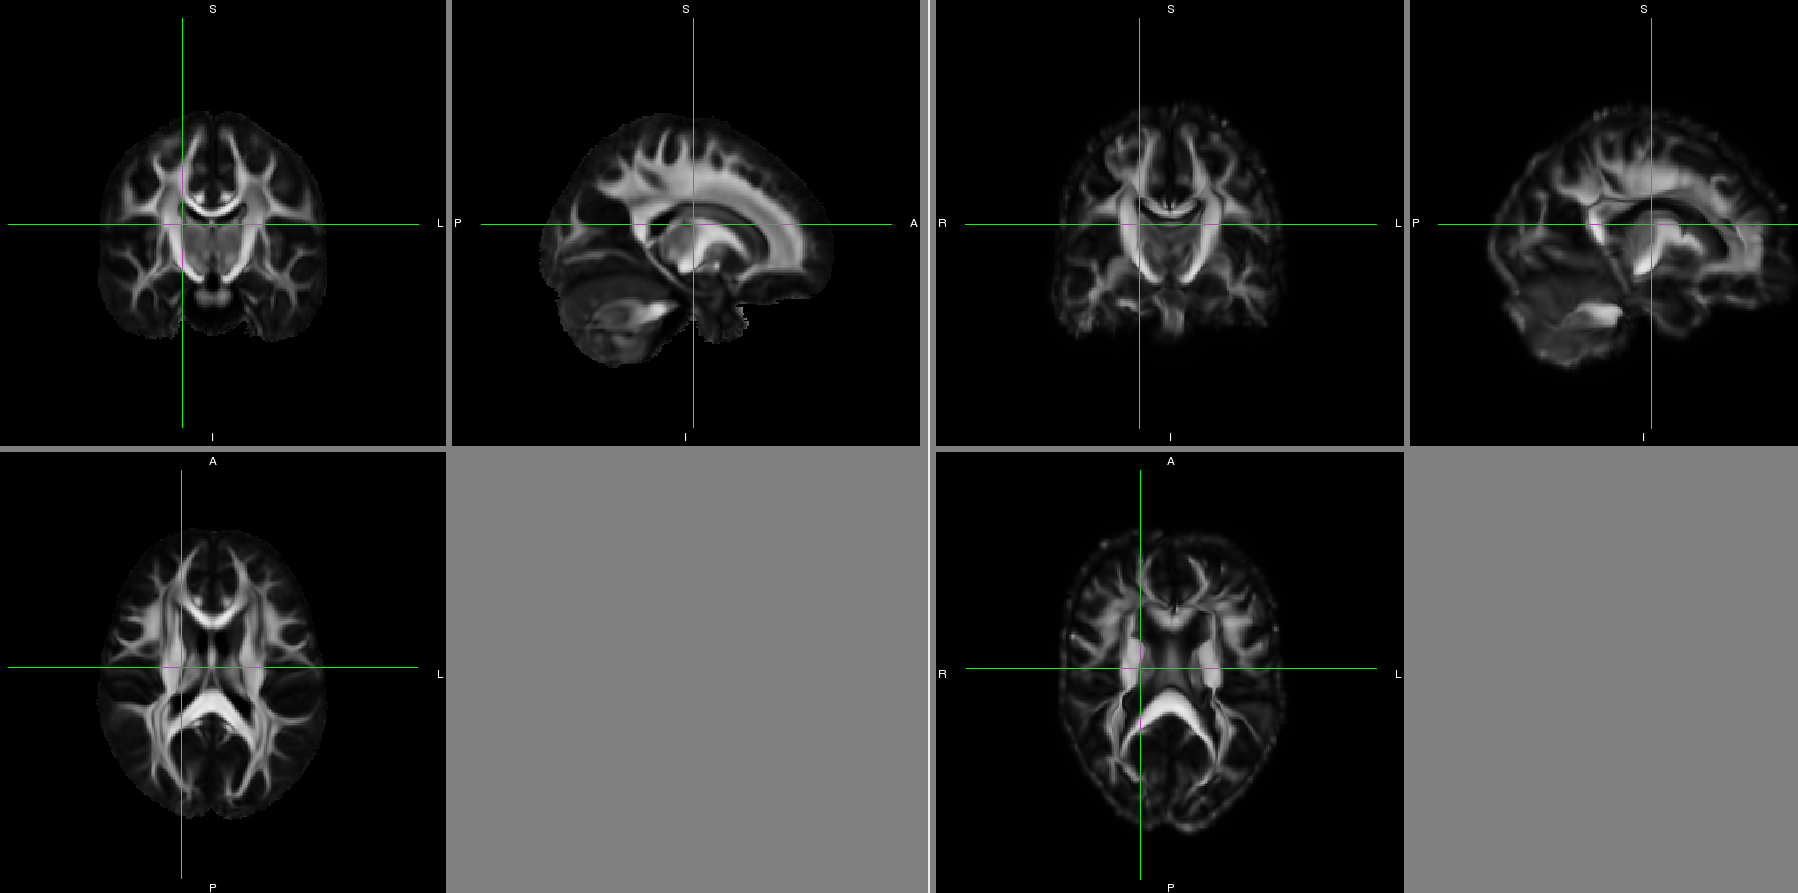

Please find attached a snap shot of the IIT atlas (left) and a single subject's template after deformable alignment to the IIT atlas (right).

I've tried registering my subject templates directly to the IIT atlas and still had the same problem.